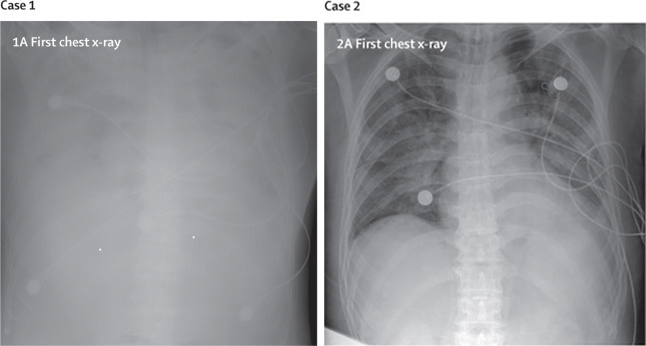

两名COVID-19感染者的胸部X光片有大面积白色阴影,显示肺部因白细胞大量浸润而严重发炎。(来源/Chen N, et al. Lancet. Epidemiological and clinical characteristics of 99 cases of 2019 novel coronavirus pneumonia in Wuhan, China: a descriptive study. Lancet 2020; 395: 507–13.)